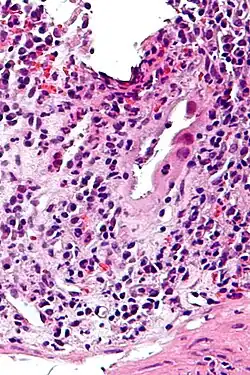

Micrograph of CMV colitis. H&E stain.

CMV colitis may be clinically manifested with diarrhea (usually non-bloody), abdominal pain, weight loss and anorexia. The diagnosis of CMV colitis is based on serology, CMV antigen testing and colonoscopy with biopsy. CMV colitis usually occurs in immunocompromised patient and is much rarer in immunocompetent patients. Although it is known that CMV colitis is almost always caused by reactivation of latent CMV infection in immunocompromised patients, new infection of CMV or reinfection of different strain of CMV can cause colitis in immunocompetent hosts. Because asymptomatic CMV viremia and viruria is common and about 1/3 of symptomatic CMV infection is caused by reinfection of different strain of CMV, the diagnosis of CMV colitis needs more direct causality. It is practically achieved by colonoscopy or sigmoidoscopy tissue sampling and pathological evidence of CMV infection under microscope, more specifically macroscopic picture will show many ulcers that appear on the mucous membrane and microscopically the biopsy will show intranuclear and cytoplasmic inclusion bodies. Positive CMV IgG doesn't necessarily mean that it is reactivation of latent infection because of the possibility of reinfection of different strain.